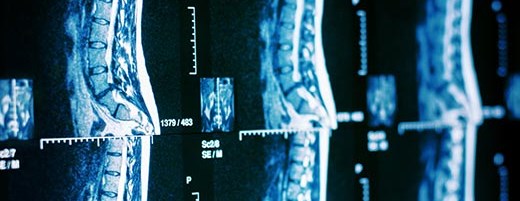

Stabilizacja kręgosłupa lędźwiowego to operacja wykonywana w celu ustabilizowania chorobowo zmienionego odcinka i zniesienia ucisku na struktury nerwowe powodującego ból. Zabieg polega na wprowadzeniu implantów łączących od tyłu objęte chorobą kręgi oraz na usunięciu patologicznie zmienionej kości i tkanek miękkich wywołujących ucisk. W razie potrzeby stosuje się także implant pomiędzy trzony kręgów dla uzyskania odpowiedniej stabilności.

Cięcie wykonywane jest pośrodku grzbietu, tylko na takiej długości, aby sprawnie wprowadzić implanty oraz dokonać odbarczenia struktur nerwowych, wyjaśnia ortopeda Rehasport Łukasz Bartochowski. Operacja polega na precyzyjnym wprowadzeniu śrub poprzez nasady kręgu do trzonów, które wymagają stabilizacji oraz na wprowadzeniu pomiędzy trzony implantu, który zapewni zachowanie odpowiedniej odległości między trzonami. Wprowadzanie śrub odbywa się pod kontrolą wzroku, dotyku, aparatu RTG, aby zminimalizować ryzyko uszkodzenia struktur nerwowych i naczyniowych. Śruby łączone są prętami dla zapewnienia prawidłowej stabilizacji. Wprowadzone implanty stają się rusztowaniem, dzięki któremu uzyskany zostanie zrost kostny pomiędzy kręgami, gwarantujący stabilność miejsca operowanego.